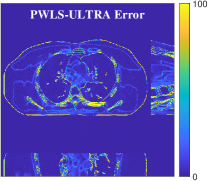

Fig.Β 5 shows the reconstructions and the corresponding error (magnitudes) images (shown for the central axial, sagittal, and coronal planes) for FDK, PWLS-EP, and PWLS-ULTRA () with the patch-based weights. Compared to FDK and PWLS-EP, PWLS-ULTRA significantly improves image quality by reducing noise and preserving structural details (see zoom-ins). Fig.Β 6 shows the RMSE for each axial slice in the PWLS-EP and PWLS-ULTRA (with the weights ) reconstructions. PWLS-ULTRA clearly provides large improvements in RMSE for many slices, with greater improvements near the central slice.

Section IV.E and Table III of [60] compared the performance of various methods for low-dose cone-beam (3D) CT reconstruction, for the XCAT phantom volume. Fig.Β 13 shows the reconstructions and the corresponding error (magnitudes) images (shown for the central axial, sagittal, and coronal planes) at for FDK, PWLS-EP, PWLS-ST (with ), and PWLS-ULTRA () with patch-based weights . PWLS-ULTRA provides better reconstructions and reconstruction errors compared to the conventional FDK and the non-adaptive PWLS-EP. PWLS-ULTRA also outperforms the proposed PWLS-ST scheme, and provides sharper reconstructions of image edges (see zoom-ins).